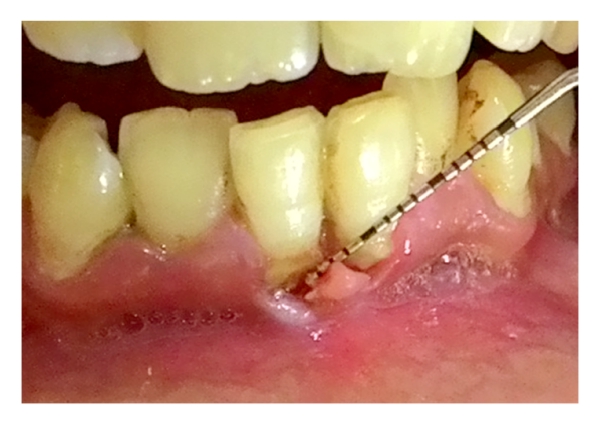

A 28-year-old male reported to us with the chief complaint of sharp pain in mandibular anterior region 2 days back. He was apparently alright 2 months back when he noticed small lesion developing in the area of chief complaint. The lesion slowly increased in size and was associated with dull pain which aggravated 2 days back manifesting as sharp pain which led him to report to the department. Intraoral examination revealed a lacerated lesion involving the attached gingiva and alveolar mucosa in relation to mandibular incisors (Figure 2) measuring 9 mm × 4 mm 2 mm. There was no exposure of bone in the affected area. He had a history of habit of picking the mandibular anterior area with a matchstick which led to this laceration. He had a history of suspension from his job a year back and admitted to being depressed for the past 6 months owing to his unemployment. On further probing, it was apparent that his picking habit seemed to have developed alongside his depression. He maintained fair oral hygiene with no evidence of any other dental discrepancy. He appeared to be well-built and healthy with no other relevant medical history. On referral to the Department of Psychiatry he was diagnosed as a case of depression with an adjustment disorder establishing that a diagnosis of gingivitis artefacta major was made based on his history and clinical findings.